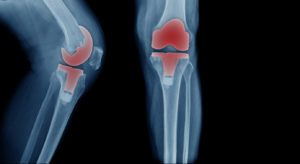

American adults undergo approximately 600,000 total knee replacements every year. This surgery involves the removal of all or part of your knee joint (cartilage and bone) and the replacement of it with prosthetic parts made of metals and plastic resins. This highly successful procedure restores arthritic or otherwise compromised knee joints, giving people pain-free, fluid